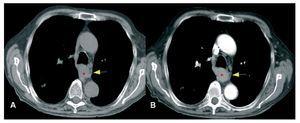

Fístula arteriovenosa pulmonar

Arnalich Jiménez, Ruiz Cobos, Casanova Espinosa, de Santiago Delgado, Hoyos Vázquez

Revista de Patología Respiratoria 2012;15:33-5

Acceso a texto completo